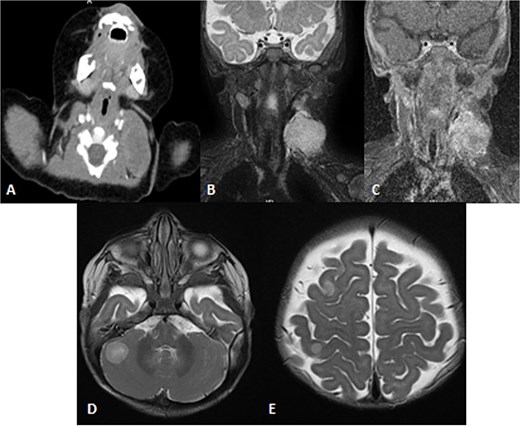

Pathology showed a round blue cell; thus, chest, abdomen and pelvis CT was done, which showed two solid pulmonary nodules and a 3.8 × 2.1 × 3.4 cm and incidental findings of neck mass involving the left sternocleidomastoid muscle. Further assessment was done by neckMRI, which shows a homogenously high-signal-intensity mass arising from the left sternocleidomastoid muscle on STIR with heterogeneous enhancement and an area of central necrosis on postcontrast images. However, during neck MRI protocoling a right cerebellar mass was identified and further images of the brain were obtained. The brain MRIs showed multiple scattered rounded lesions that showed high signal intensity at the gray–white matter junction seen at right frontoparietal lobes and in the right cerebellar hemisphere, findings in keeping with brain metastasis (Fig. 8). To treat the hydrocephalus, an external ventricular drain was implanted. Unfortunately, the patient passed away as a result of brainstem metastases as the disease worsened.

Patient underwent brain and neck MRI after incidental findings of left neck mass on chest CT. (A) Axial enhanced chest CT and the imaged part of the neck show a large heterogeneously enhanced left neck mass mostly arising from the left sternocleomastoid muscle with central necrosis causing mild mass effect upon left internal jugular vein with no sign of invasion or thrombosis. (B and C) Coronal STIR and postcontrast T1 fat-saturated images show homogenously high signal of the left neck mass arising from the left sternocleomastoid muscle on the STIR image with heterogeneous enhancement and central necrosis on the postcontrast image. (D and E) Axial T2WI images show multiple scattered, rounded high-signal-intensity supra- and infratentorial lesions at the gray–white matter junctions involving right frontoparietal lobes and the right cerebellar hemisphere, in keeping with brain metastasis.